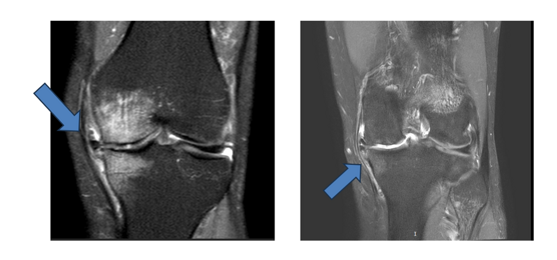

Diagnosi

La diagnosi di artrosi si basa su visita specialistica ortopedica, valutazione clinica, radiografie e talvolta risonanza magnetica.